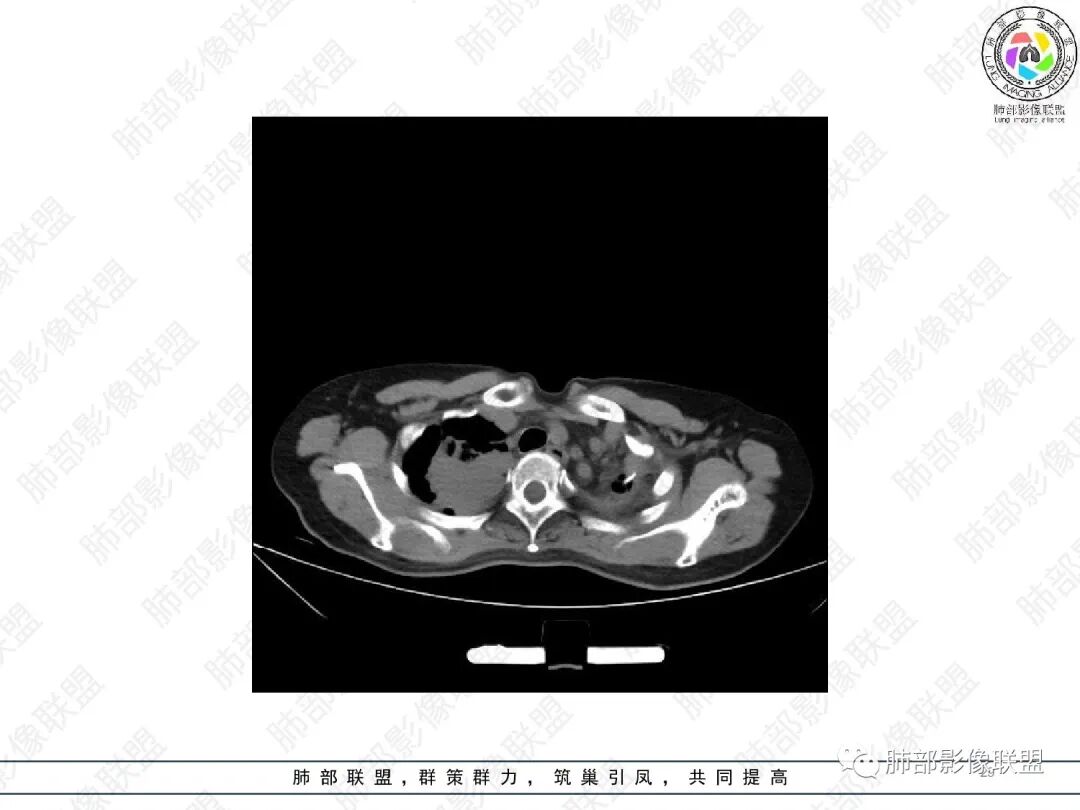

女,51,咳嗽、咳痰半年。左下叶手术史,术后抗TB治疗史。胸部CT:右肺上叶尖段团片影,边界较清,部分层面周围清楚GGO;形态不规则,近端呈指套样改变;密度不均,内见斑点状高密度灶;胸膜牵拉。右肺中叶内侧段斑片实变影,邻近多发小树芽影?左侧胸廓塌陷,左上叶多发小结节影,支气管扩张样改变,左上叶支气管腔可见钙化影。考虑TB,鉴别ABPA、腺Ca等。

2.胸部CT:右肺上叶及中叶不规则块状影,沿支气管走行方向指套样影,支气阻塞湖嵌塞,腔内可见高密度影。灶周可见磨玻璃,外围见结节影及树芽征。左肺体积缩小,见不规则条索影、胸膜增厚,纵隔牵拉左移。

胸部影像学的特异性改变:随着胸部高分辨率CT(HRCT)的普及,ABPA常见肺部影像表现包括黏液嵌塞、支气管扩张、小叶中心性结节、树芽征和马赛克征等。根据是否有中心性支气管扩张,ABPA可分为变态反应性支气管肺曲霉病-血清IgE增高型(ABPA-S)和变态反应性支气管肺曲霉病-中心性支气管扩张型(ABPA-CB)。气道黏液嵌塞在ABPA很常见,胸部HRCT上表现为指套征或牙膏征。气道黏液栓通常为低密度影,但20%也可为高密度黏液影(high-attenuation mucus,HAM),定义为气道内黏液栓密度高于脊柱旁肌肉的 HRCT值,这也成为ABPA特征性的影像表现之一,外周细支气管黏液阻塞可见“树芽征”。中央性支气管扩张曾一直是ABPA诊断标准之一,但其用于诊断ABPA的敏感度仅为37%。此外,33%~43%的中央性支气管扩张也可延伸至外周,26%~39%的ABPA只有周围性支气管扩张。因此,目前认为中央性支气管扩张应视为ABPA的并发症,而非其诊断标准。